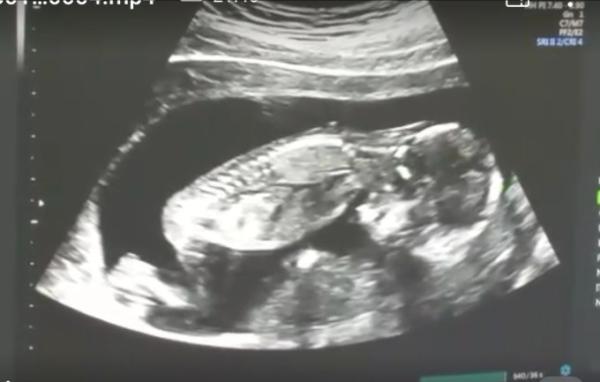

Bin auch zurück vom FA aber irgendwie nicht begeistert von dem Termin. Es war eigentlich eine normale VU und Kontrolle vom khaus Aufenthalt wegen dem Hämatom. Es gab nur äußerliches US. Er sagte das Baby sieht gut aus und ist zeitgerecht 16. Woche. Auf die Frage wegen dem Hämatom, schaute er erstmal nach und fragte wie groß es am Anfang war. Jetzt soll es angeblich 3cm sein. Ok sieht echt Grund aus also konnte 3x3x3 hinkommen. Genauer ging er aber darauf nicht ein. Ich sagte ihm auch das ich seit dem khaus abblute, halt dunkel braun aber hier und da wenn ich lange gelegen habe mit dunklem Schleim, da meinte er nur: puddingartig? Ich joar könnte man so sagen, seine Antwort: ja ist altes Blut. Ich trage ne Binde wegen dem Mist, aber sehen wollte er es nicht. Ich musste weiter bohren wie es weiter geht und meiner Körpertemperatur. Seine Antwort: soll mich weiter schonen und 37,5° ist normal. Hmm.... Auf die Frage wie es aussieht das ich das Gefühl habe das auch mein Unterbauch immer wieder verhärtet, soll ich zu den 6 Magnesium Tabletten noch eine dazu nehmen wenn es hart wird.... Irgendwie war das alles so wischi waschi. Ich kam mir so dumm vor, und wirklich beruhigter bin ich jetzt auch nicht. Ich soll nächste Woche wieder kommen wegen Krankmeldung da werde ich versuchen nochmal mit ihm zu reden. Weiß nicht ob er sich im klaren ist wie sehr mir das alles sorgen macht. Und auf dem Ultraschallbild erkenne ich ja Mal so gar nichts. Zeuge euch Mal mein letztes US Bild vom Krankenhaus das war 15. SSW am 2.1

Achso das vom khaus ist en Screenshot da haben wir ein Video gemacht